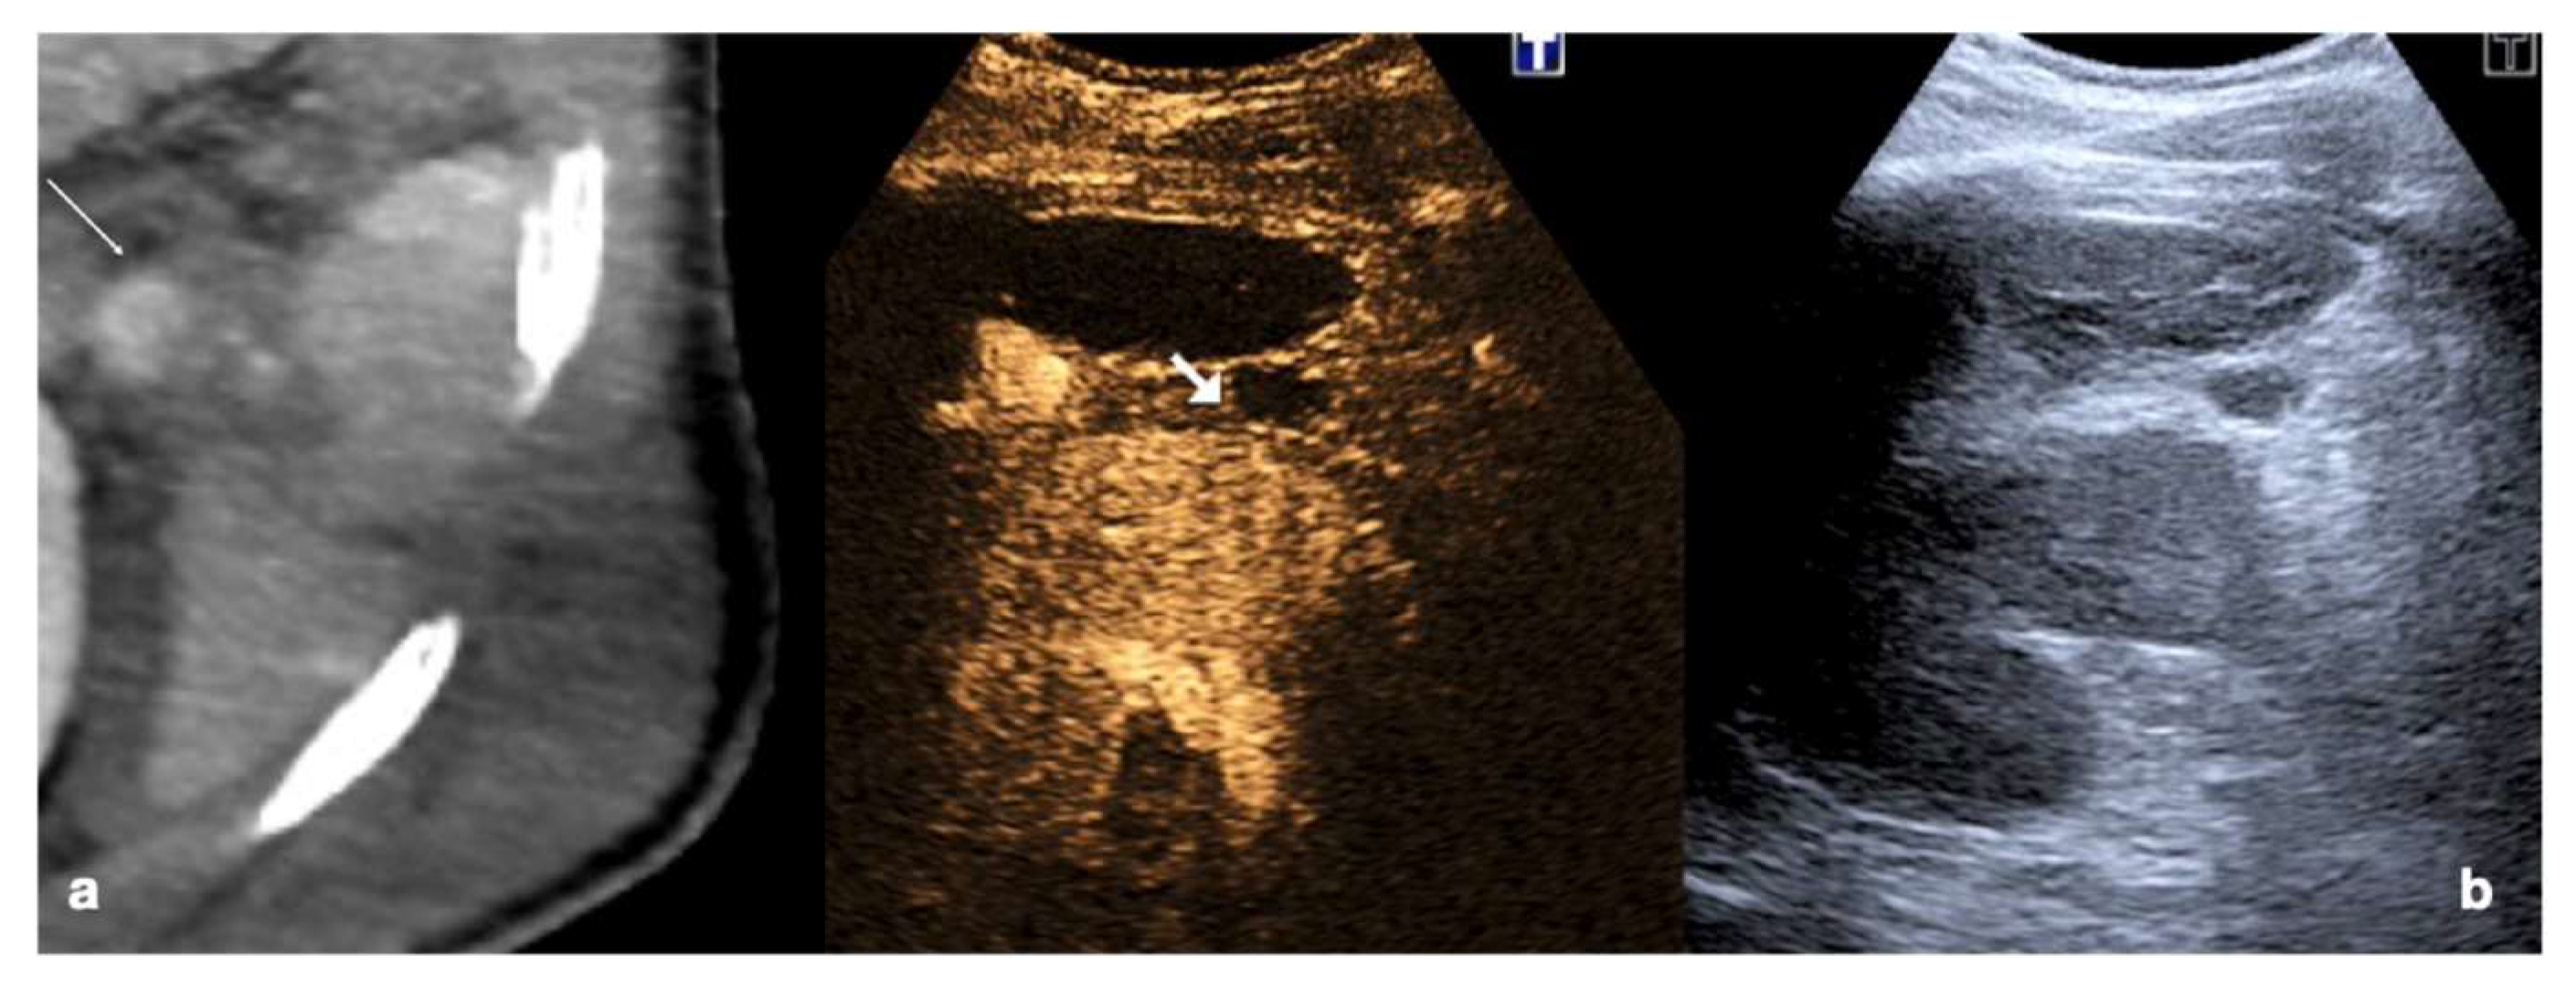

- Parenchymal injuries:

2.3.2. Vascular Injuries